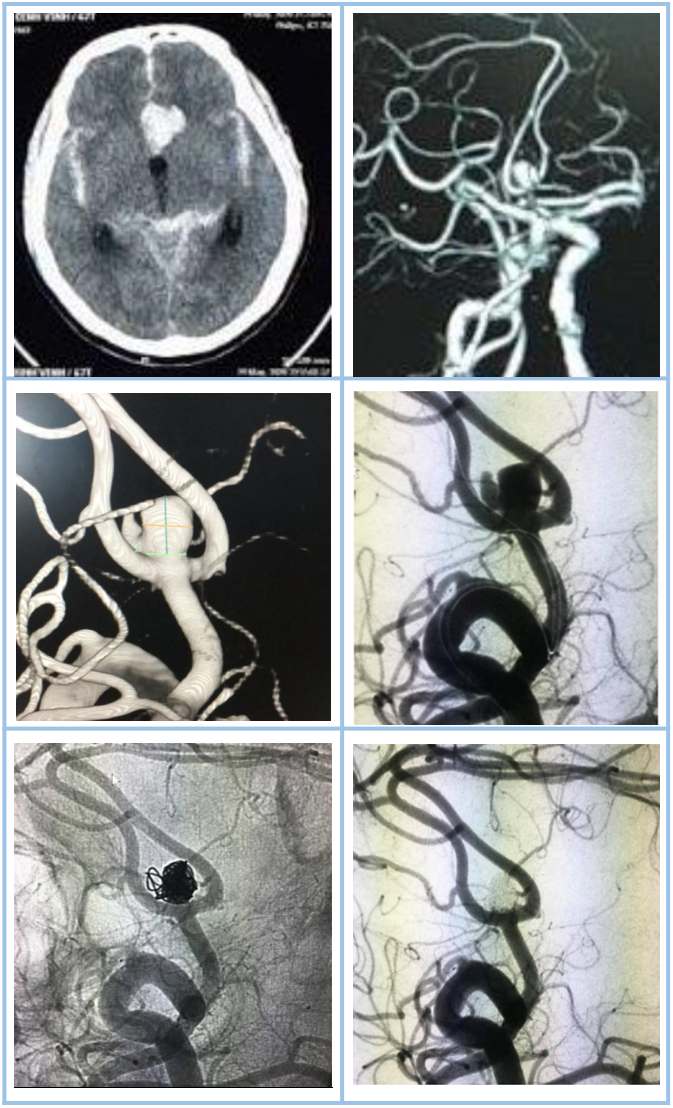

Phình động mạch não vỡ là nguyên nhân của 85% các ca chảy máu dưới nhện không do chấn thương.

Phình động mạch não được phân loại theo hình dạng bao gồm phình hình túi (saccular aneurysm), phình hình thoi (fusiform aneurysm), phình do lóc tách mạch (dissecting aneurysm), phình dạng fusi-sacciform trong bệnh lý giãn phình (dolichoectasia), phình dạng bọng nước (blister aneurysm). Phình hình túi chiếm phần lớn trong số phình mạch não. Phình hình túi được chia làm hai loại liên quan đến việc điều trị bao gồm phình cổ hẹp và phình cổ rộng. Phình cổ rộng được định nghĩa là túi phình có cổ ≥ 4mm hoặc tỉ lệ đường kính đáy/cổ <1.5.

Việc chẩn đoán và điều trị gây tắc phình động mạch não vỡ được thực hiện theo các khuyến cáo của hiệp hội đột quỵ Châu Âu và Mỹ. Chẩn đoán phình mạch não vỡ dựa vào chụp CT mạch máu, cộng hưởng từ mạch máu hoặc chụp mạch số hóa xóa nền (DSA) trong đó chụp DSA là tiêu chuẩn vàng để chẩn đoán.

Hai phương pháp được lựa chọn bao gồm phẫu thuật hoặc can thiệp nội mạch. Việc lựa chọn phương pháp điều trị tùy thuộc vào hình dạng, vị trí, kích thước túi phình cũng như tuổi, các bệnh lý đi kèm cũng như là lựa chọn của bệnh nhân. Thử nghiệm lâm sàng ISAT (International Subarachonoid Aneurysm Trial) khuyên chọn can thiệp nội mạch nút coils nếu túi phình vỡ có thể được điều trị bởi cả hai phương pháp là như nhau. Hơn nữa, các túi phình có cổ nhỏ hay ở vòng tuần hoàn sau, bệnh nhân cao tuổi thì nên điều trị bằng nút coils. Các yếu tố ủng hộ phẫu thuật bao gồm các túi phình có cổ rộng, có nhánh mạch tách từ túi phình, phình động mạch não giữa, phình quanh trai hoặc bệnh nhân có khối máu tụ nhu mô đi kèm.

Trong can thiệp nội mạch, phương pháp nút coils đơn thuần được ưu tiên lựa chọn đối với phình hình túi cổ hẹp. Đối với phình hình túi cổ rộng thì có thể lựa chọn can thiệp nút coils có bóng chẹn cổ hoặc nút coils có stent hỗ trợ hoặc đặt lồng WEB. Đối với phình hình thoi, phình lóc tách đã vỡ thì phương pháp bảo tồn (bằng đặt stent chuyển hướng dòng chảy) hoặc phương pháp gây tắc mạch nuôi có hiệu quả gây tắc túi phình tương tự nhau tuy nhiên phương pháp bảo tồn nên được ưu tiên nếu có khả năng thực hiện. Đối với phình hình bọng nước (blister aneurysm), việc điều trị hiện nay còn gặp nhiều khó khăn và còn nhiều tranh cãi thì đặt stent chuyển dòng hiện đang là phương pháp được cân nhắc đầu tay để điều trị.

Bệnh nhân nam 67 tuổi có xuất huyết dưới nhện lan tỏa (Fisher 4) do vỡ túi phình thông trước (phát hiện bằng CT mạch máu). Túi phình sau đó được can thiệp nút tắc hoàn toàn bằng coils có bóng hỗ trợ.